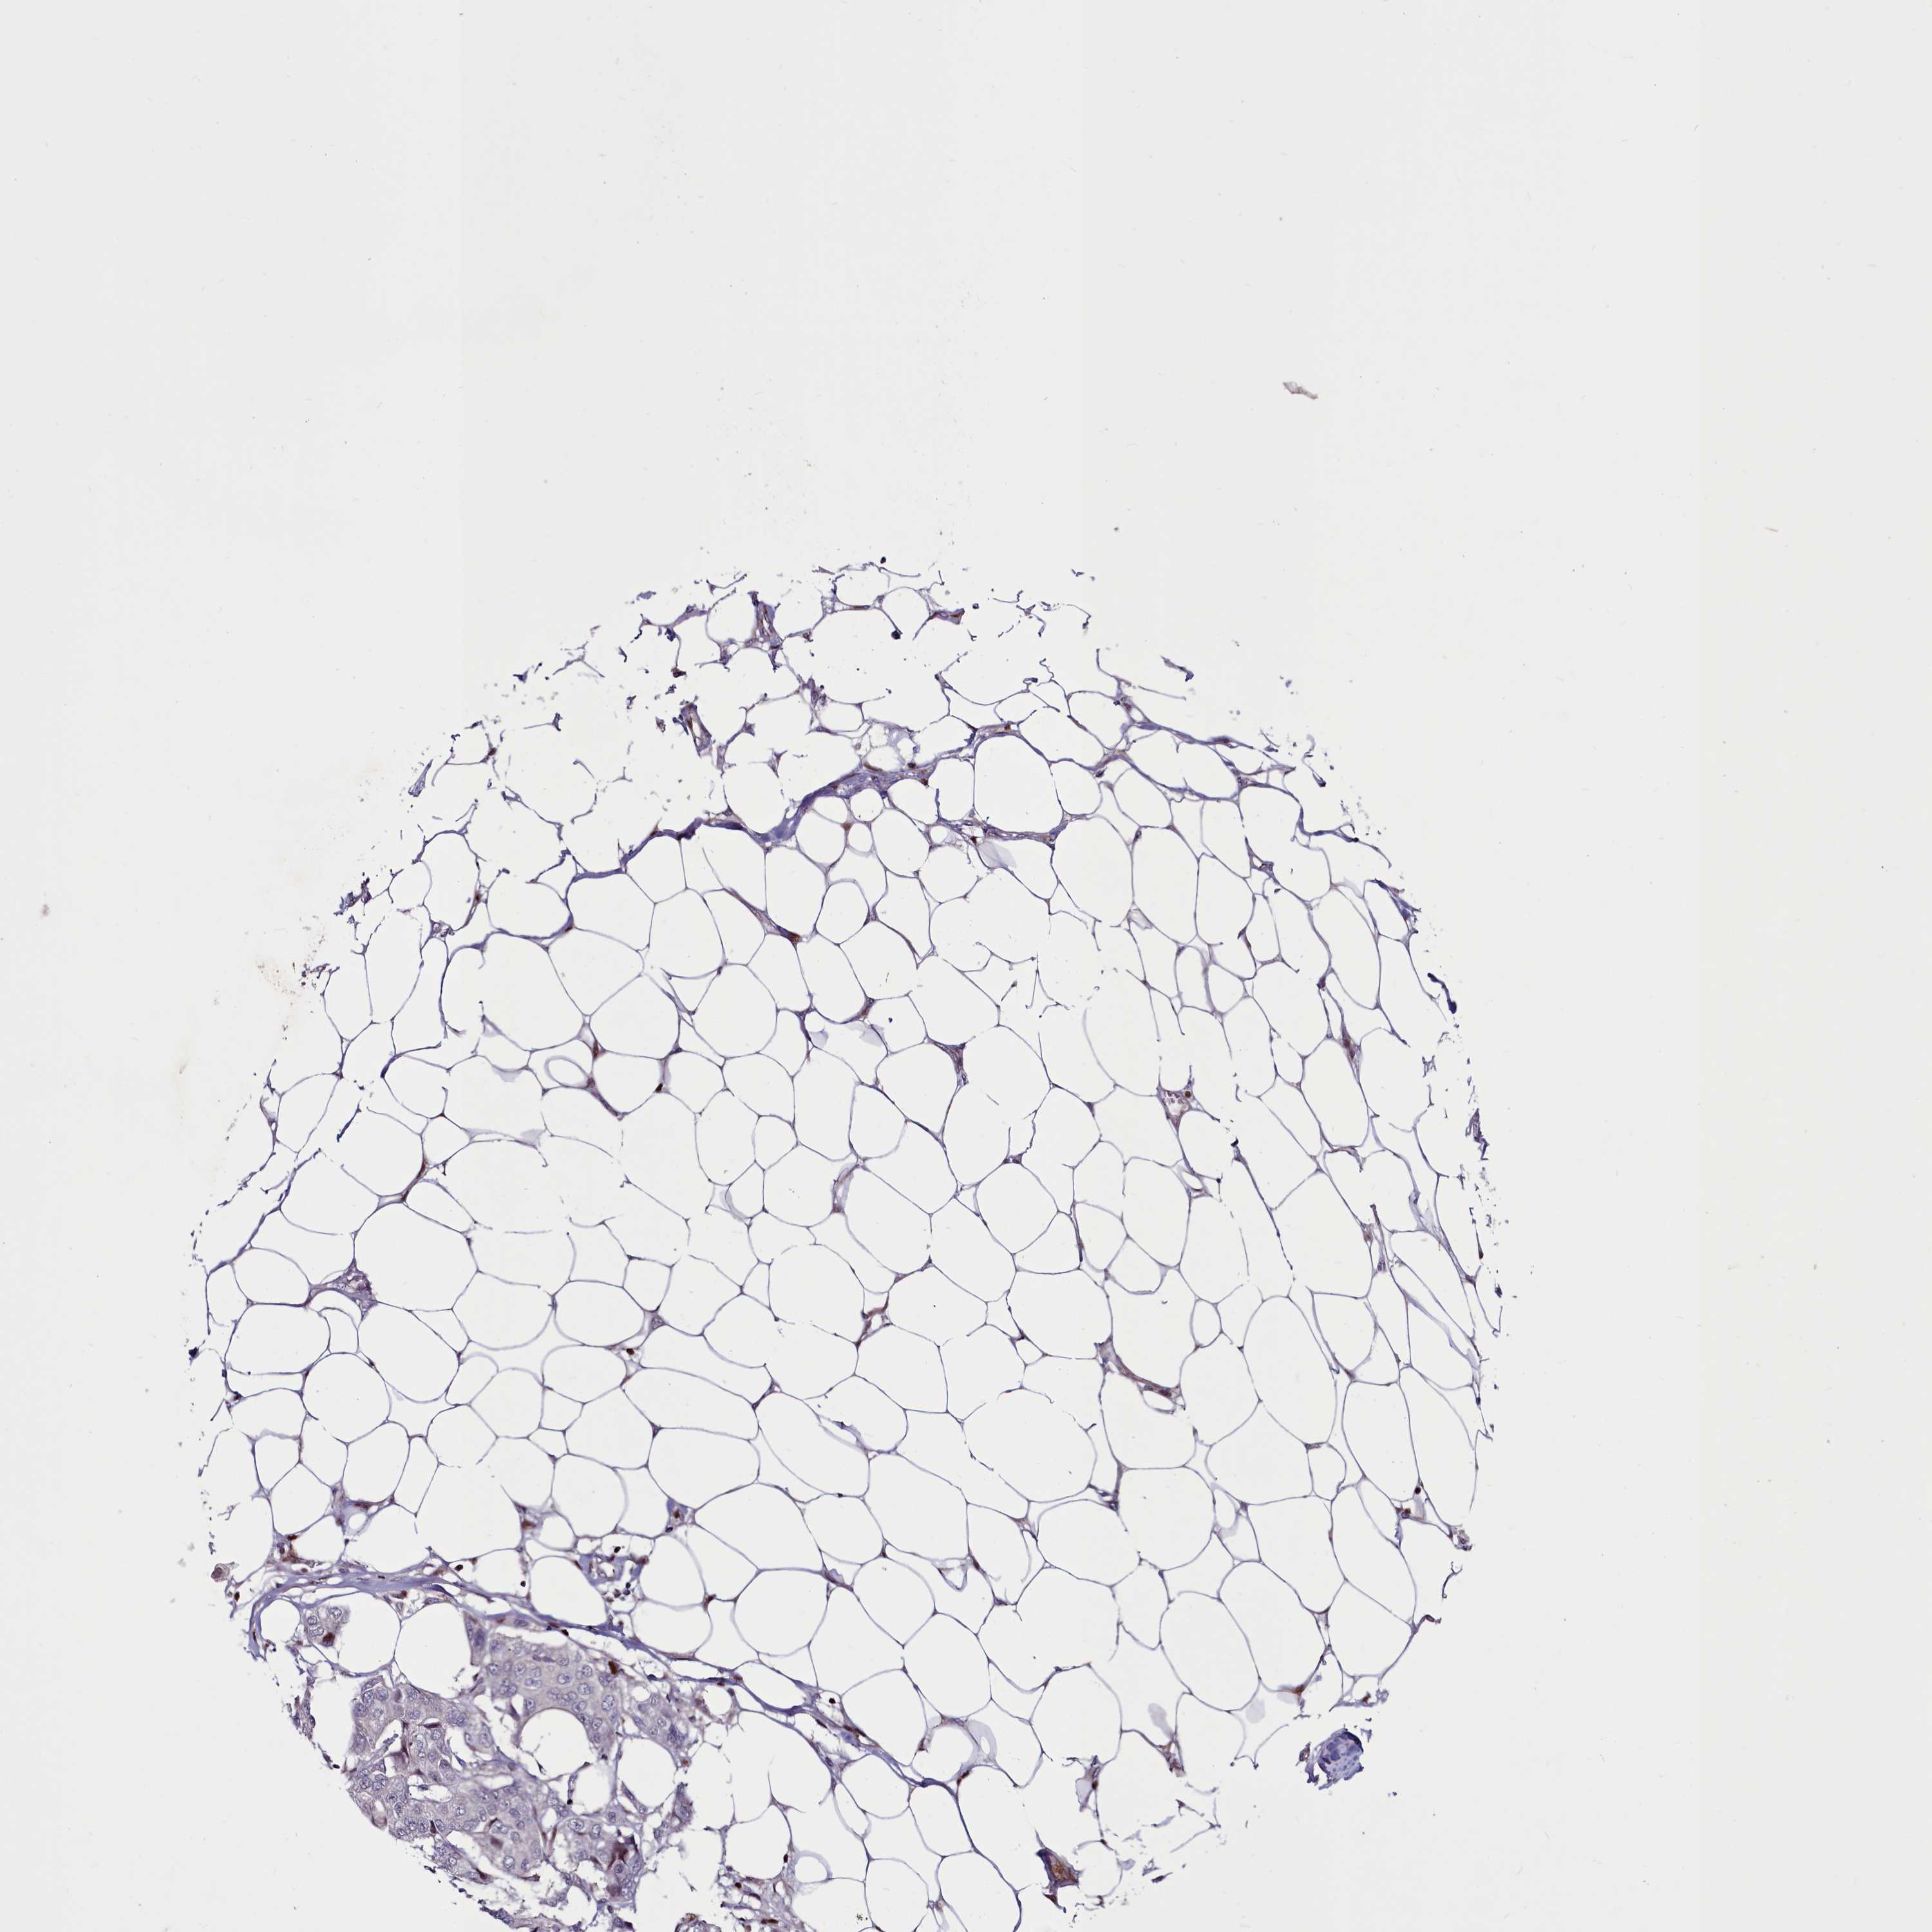

CANCER BREAST CANCER Show tissue menu

BRCA TCGA BRCA VALIDATION PROTEIN EXPRESSION